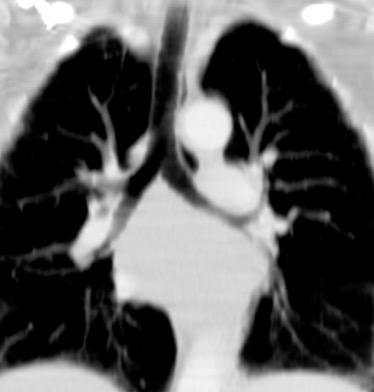

6. ÁREAS DEL MEDIASTINO EN TC